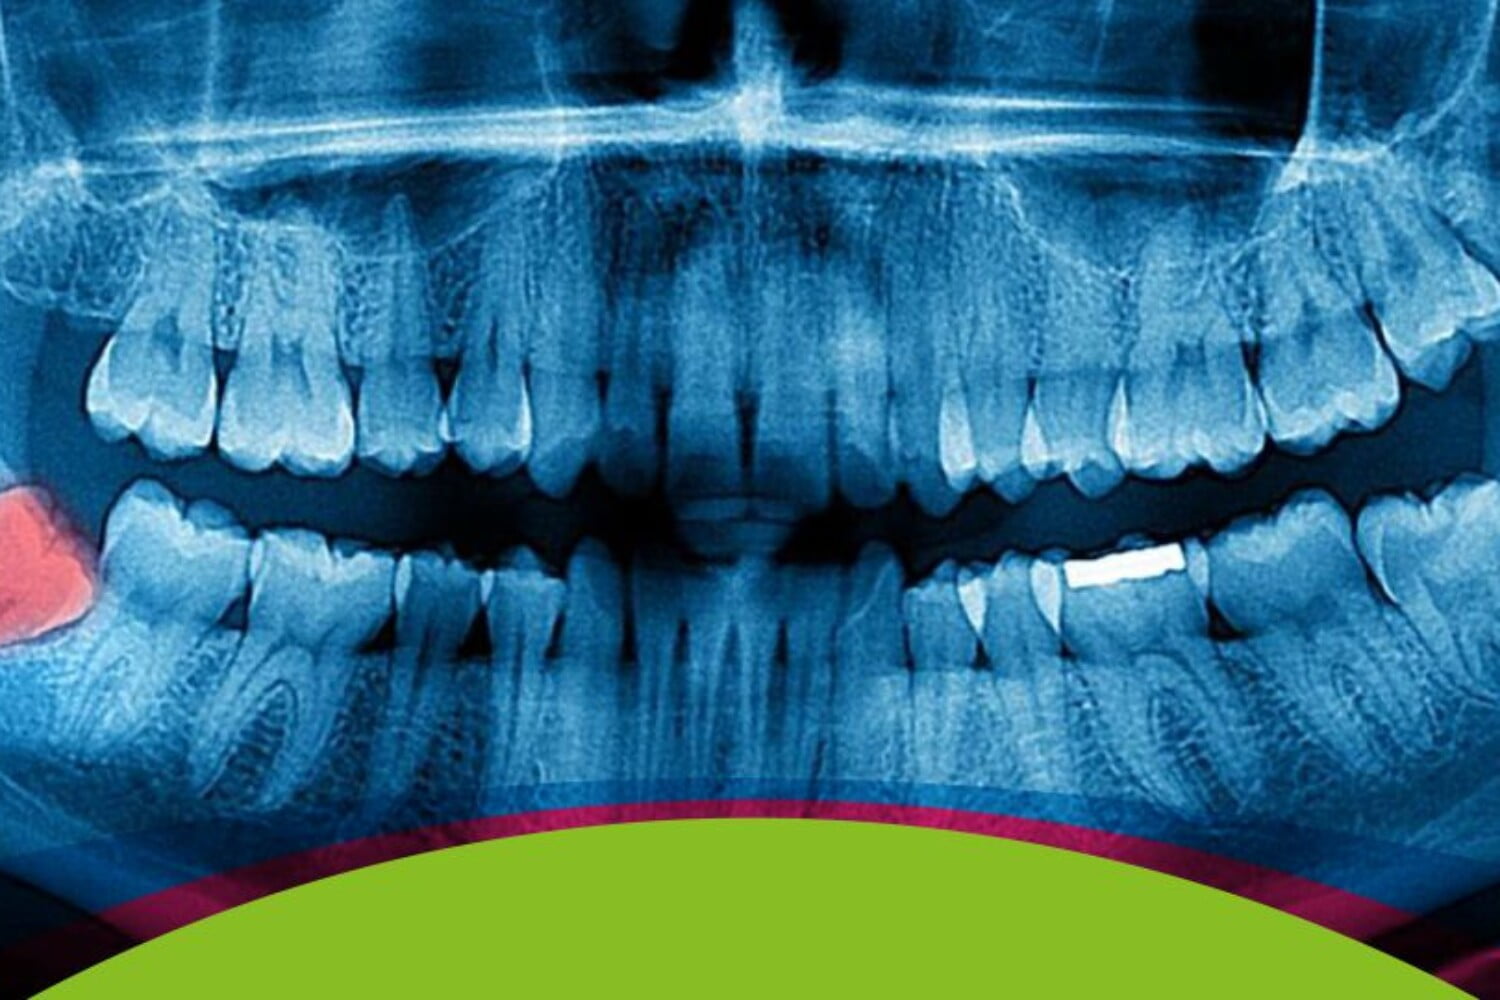

La decisión de extraer o no los cordales no puede hacerse a la ligera. Tu dentista de confianza debe realizar un buen diagnóstico, sirviéndose de radiografías o escaneado digital. Sólo así podemos determinar las causas reales de las molestias.

- Radiografía PANOREX®